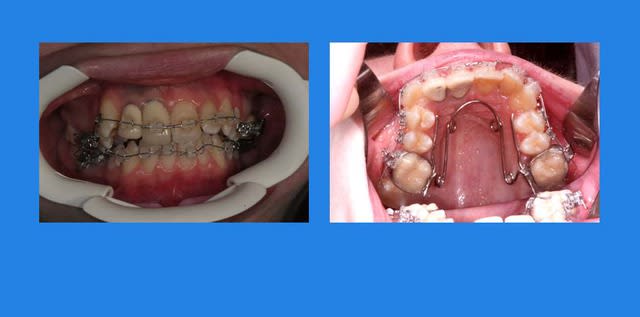

13/03/2010 à 23h44

Puis elle ne vient pas pendant plus de 2 mois

et, oh surprise (mauvaise)

c’est la cata !!!

4 pzmuzx - Eugenol

Images 1 qtgoxf - Eugenol

j’ai fait plusieurs erreurs,

1°) ne pas insister plus pour la revoir, sans doute, inconsciemment, parce que comme c’était une copine de mon neveu, je lui avais fait un prix

2°) mettre un appareil puissant, de par ses bras,(mélanger les forces fortes et les forces faibles), sans imaginer que la patiente pourrait avoir des contraintes personnelles qui l’empêcherait de venir à son RDV. j’aurai du mettre un transpalatin ou un Q.H. sans bras

c’est ce que je fais maintenant

3°) déposer le Q.H. au lieu de couper simplement les bras, j'ai perdu de la place, car tous les vieux ortho savent que la seule manière de reculer une molaire, c’est de la déroter

@+ Bjc.